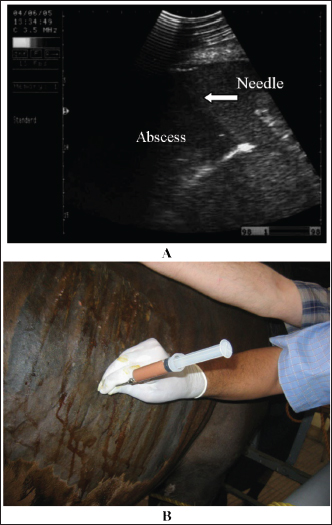

Fig. 4. Sonogram of 5 horses with spasmodic colic. Images A and B were taken at the right flank region and showed the echogenic cecal tissues with variable echogenicity and increased wall thickness. The peristaltic movement of the cecum was hypermotile during real-time scanning. Image C shows the spleen, descending colon, and left ventral colon obtained from the left 13th intercostal space. They appear normal, and only hyperperistalsis was detected. Image D shows the spleen and left ventral colon from the left 13 intercostal spaces. The spleen had a normal echotexture, the left ventral colon also had a normal echogenic wall, and only hypermotility of the left ventral colon was observed. Image E shows the spleen and descending colon. The spleen appears normal, and the descending colon appears as a circular echogenic wall with fluid and ingesta contents that appear with swirling motility more than expected.

Intestinal ultrasonography generally shows increased intestinal peristalsis. The cecal wall appears echogenic, and the contents are of variable echogenicity. The wall thickness is increased, and the peristaltic activity of the cecum is detected as hypermotile on real-time ultrasonography (le Jeune and Whitcomb, 2014). The left ventral colon appears with increased wall thickness, and sacculations are detected in some cases, whereas, in others, it appears with normal wall thickness. The descending colon has a thin echogenic wall and contains isoechoic ingesta that appears in continuous motion (Fig. 4).

Spasmodic colic is usually characterized in horses by brief intermittent attacks of abdominal pain, pawing, rolling, and kicking the belly for a few minutes, then shaking and standing in a normal way for a few minutes until the next fit of pain reoccurs. Therefore, the affected animal presented with multiple skin wounds (Fig. 3). The horse suffering from spasmodic colic had increased peristaltic activity, which might be attributed to inflammatory conditions such as enteritis and colitis (Fikri et al., 2023). The ultrasonographic appearance of the abdominal organ showed that the cecum appeared with an echogenic wall, and the contents were of variable echogenicity. The wall thickness increased, and the peristaltic activity of the cecum was hypermotile on real-time ultrasonography. The left ventral colon appeared with increased wall thickness, and sacculations were detected in some cases, whereas, in others, it appeared with normal wall thickness. The descending colon has a thin echogenic wall and contains isoechoic ingesta that appear in continuous motion, indicating hypermotility of the bowel (Tharwat et al., 2008).